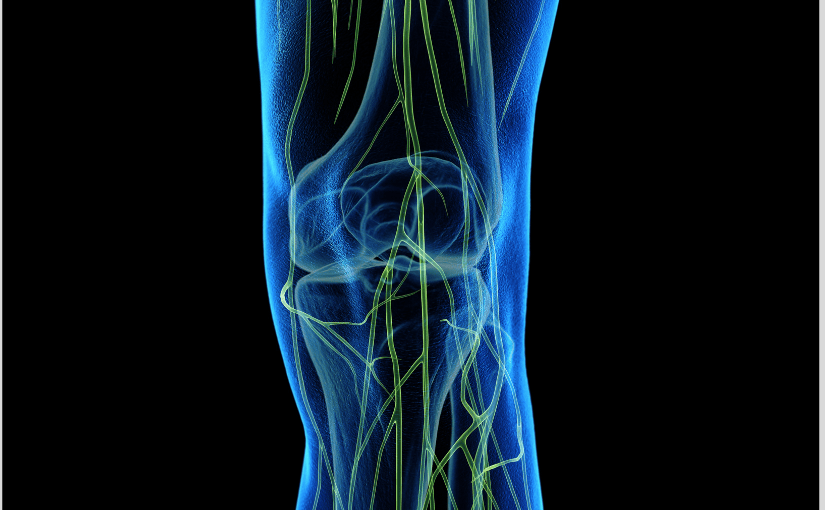

What Are the Main Pelvic Structures and How Do They Affect Movement?

When something feels off in your hips or lower back, your pelvis is often at the center of it. A chiropractic doctor looks at how each pelvic structure works together to support movement, balance, and stability.

Here’s a closer look at the key players and what they do: